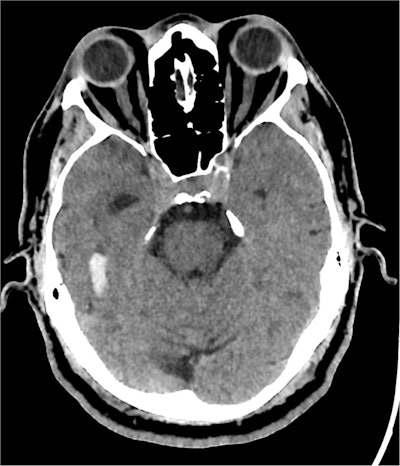

CT image of the head with a right temporal parenchymal hemorrhage, from the previous analysis using GPT-4V. GPT-4V correctly identified the image modality, anatomical region, and pathology of “intracranial hemorrhage”.Brin et al; European Radiology

Results from the previous study showed that GPT-4V had performed well in identifying modalities but only performed moderately well in anatomical localization and pathology identification. Furthermore, GPT-4V produced frequent diagnostic hallucinations. The authors concluded that the software held promise but could not be used as a standalone.

For the 230 exams, GPT-4V had demonstrated 100% modality identification; anatomical localization was 87.1% accurate, and pathology-level identification was 35.2%. The overall hallucination rate was 46.8%.

In comparison, GPT-5 also demonstrated 100% accuracy in identifying the modality used. Its performance was significantly better than that of GPT-4V with regard to anatomical localization: 97.8% overall; 100% for CT, 98.1% for x-ray, and 94.6% for ultrasound. Improvements in pathology identification were less pronounced, at 40% overall.

The authors added that the improvement in pathology accuracy was largely seen in ultrasound, with the rate rising from 9.1% to 33.8%. Pathology showed a more modest improvement for x-ray (67.9% for GPT-5 vs. GPT-4V’s 66.7%.) However, the accuracy rate for pathology-level identification for CT was lower for GPT-5 than for GPT-4V: It had decreased from 36.4% to 30.1%.

Even with the improvements in anatomical and pathology identification, the authors determined that GPT-5 exhibited the same shortcomings with errors as GPT-4V. In fact, the rate of hallucinations had worsened: 60% of the total number of exams with the updated software now had at least one hallucinated finding, while that percentage had been 46.8% with the previous version. The percentages by modality were all higher -- 73.8% for CT (GPT-4V: 51.5%), 26.4% for x-ray (GPT-4V: 19.6%), and 64.9% for ultrasound (GPT-4V: 60.6%).